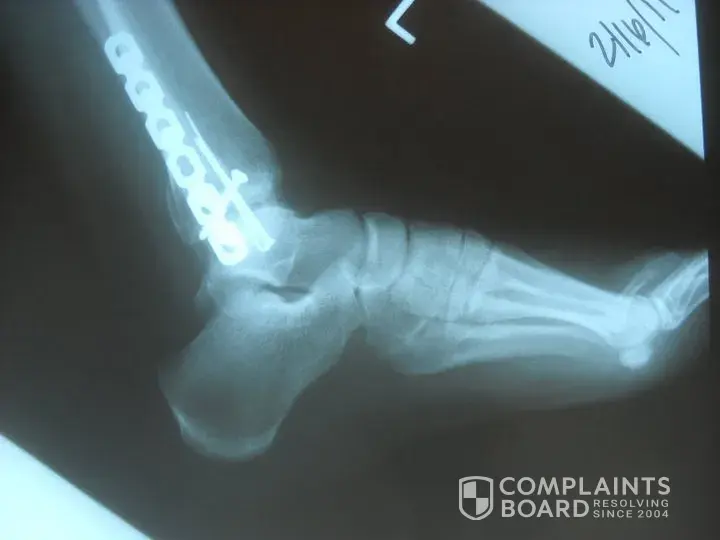

Two weeks after purchase... shattered my ankle breaking the tibia, fibula and talus. Interesting part is we had just had a health fair and my bone density came back great. Simply turned to open the back of a vehicle and foot stayed planted but leg gave. Surgey (5 pins, plate and additional screw), 34-36 visits to physical therapy, still ice 6 months later, still swells in the ankle and uo the leg, still difficult to walk when I stand to much. Quality of life is not what it was prior to fall. Hard to go down stairs, curbs, get in or out of the pool or hot tub, hard to do some chores since my ankle tires out. Have a job where I have to stand a lot and by the end of the week, walk with a more pronounced limp than when I have rested it. Have to ice daily and once I ice have to use crutches for the rest of the night or let the ankle rest for at least 6 hours.

i made the educated assumptiohn about being overweight and the cankles. if you look at the xray, you can see it